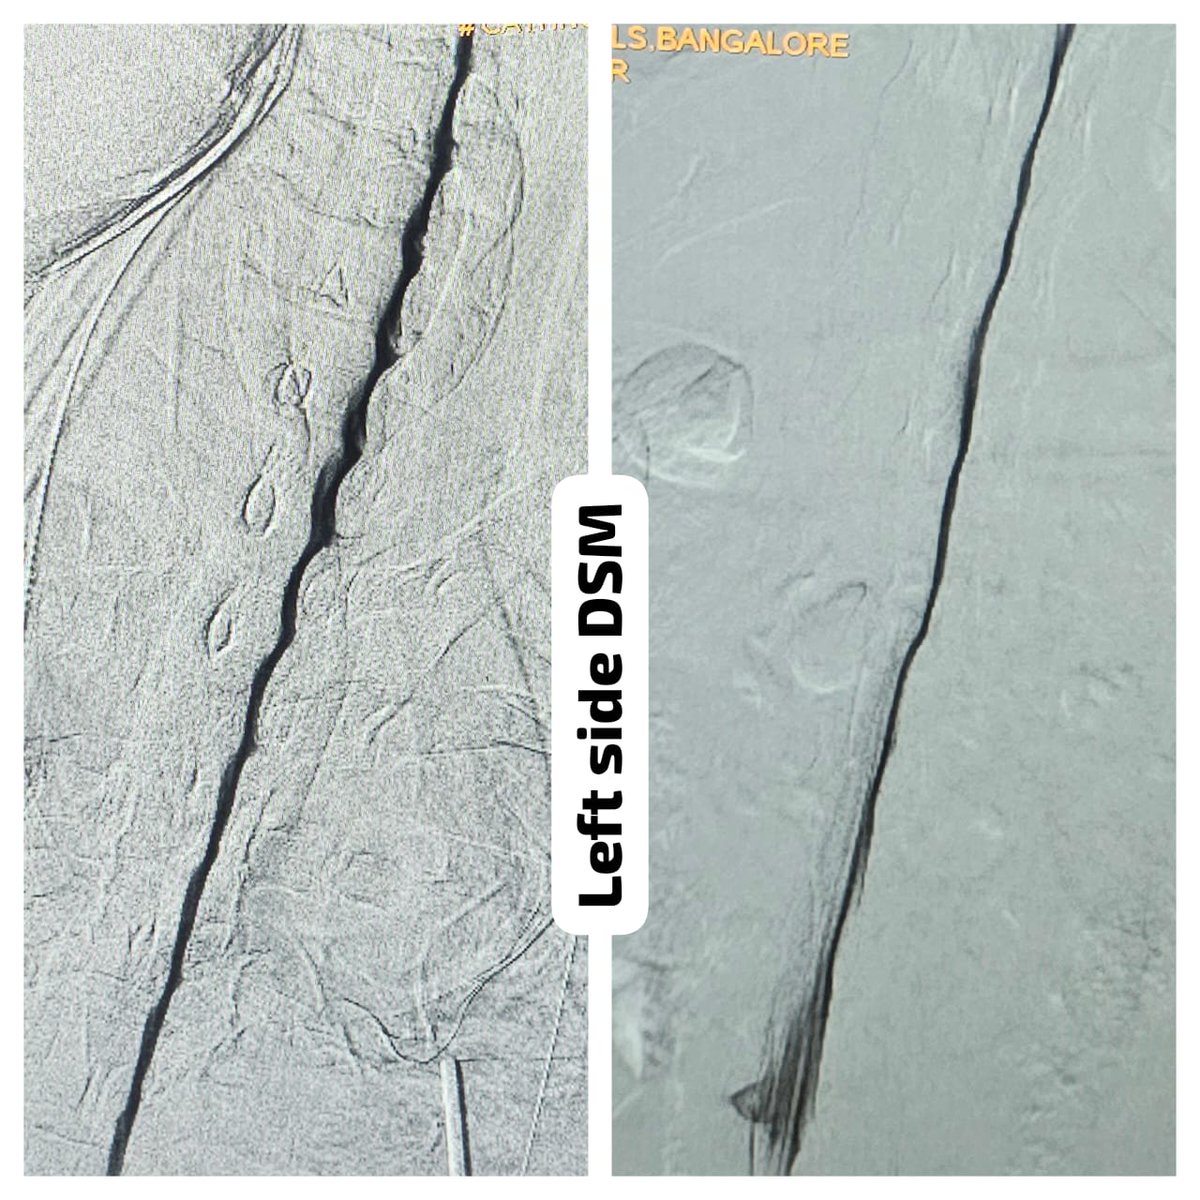

One of the very few centers in the country to offer Digital subtraction Myelography (DSM) @ApolloKarnataka for the Spinal CSF leak patients by our team @SavithKumarINR good news to our patients in India @SpinalCSFCanada @spinalCSFleak @CsfLeakIreland @csfleakinfo #SpinalCsfLeak

SharathKumarGG7's tweet image. One of the very few centers in the country to offer Digital subtraction Myelography (DSM) @ApolloKarnataka for the Spinal CSF leak patients by our team @SavithKumarINR good news to our patients in India @SpinalCSFCanada @spinalCSFleak @CsfLeakIreland @csfleakinfo #SpinalCsfLeak